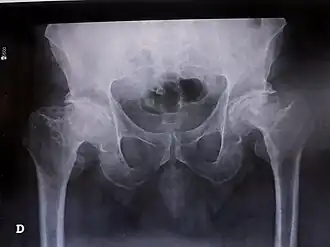

| Síndrome de Legg-Calvé-Perthes num adulto do sexo masculino com 52 anos (radiografia) | |

Nos locais onde foram feitos estudos varia entre 0,45 a 11,1 em 100.000 indivíduos. Atinge mais crianças do sexo masculino do que do sexo feminino (4:1), sendo que os sintomas costumam ser mais graves em crianças do sexo feminino (Ortner, 2003; Guarniero et al., 2005b). Em relação à idade, a síndrome pode-se observar em crianças entre os 2 e os 16 anos, mas a idade com uma incidência mais frequente é aos 6 anos. A maioria dos casos apresentam-se de forma unilateral, mas em 8% a 24% dos casos existe bilateralidade que demonstra ser sucessiva e não simultânea (Khan et al., 2018). Nos casos unilaterais, não existe diferença significativa entre o lado esquerdo e o lado direito (Harrison et al., 1976; Guarniero et al., 2005a). Pode, também, surgir em adultos embora seja mais raro.